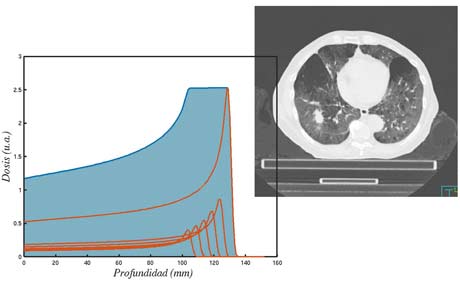

El cálculo de la dosis en los tratamientos de radioterapia externa es un desafío por la alta conformación de los haces de radiación en la tecnología actual (IMRT y VMAT). Estas técnicas adaptan los haces a la forma del tumor, de manera que la dosis recibida por los tejidos sanos es pequeña, pero el coste asociado es que cualquier error de posicionamiento o el movimiento del propio tumor (por ejemplo, por respiración) puede afectar a la dosis depositada.

La dosis recibida por el tejido sano es de especial importancia cuando los pacientes son pediátricos o cuando se van acumulando tratamientos radioterápicos. Para este tipo de tratamientos está especialmente indicada la radioterapia con protones, disponible en la sede de Madrid de la Clínica Universidad de Navarra. En esta línea buscamos resolver los problemas asociados al Pencil-Beam Scanning y el movimiento interno del tumor.

En esta línea buscamos optimizar el procedimiento y la dosis en el caso de tumores pulmonares y oculares empleando desarrollos propios tanto de equipamiento como de herramientas computacionales